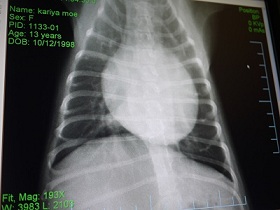

レントゲンを見ながら先生が、

『携帯で写真とか撮ってもいーよ。』って言ってくれてね。

持参していた一デジさんで撮影させていただきました。

コレね。

上↑の写真と全く同じなんですけど・・

今迄、レントゲンを見せてもらってても、

白くハッキリと確認できる部分だけが心臓なんだと思ってたらね

赤く色付けした部分は肥大してしまってるところだよ。って教えてもらってね。

(ちょっと大袈裟に書きすぎたかも^^; )

黄色は気道です。

・・そりゃ。咳・・出るわぁ・・(T▽T;)

気道を圧迫どころか、重なるように押し上げてる状態だものね・・。

レントゲン1枚にしても 何って分かりやすいんでしょう・・。